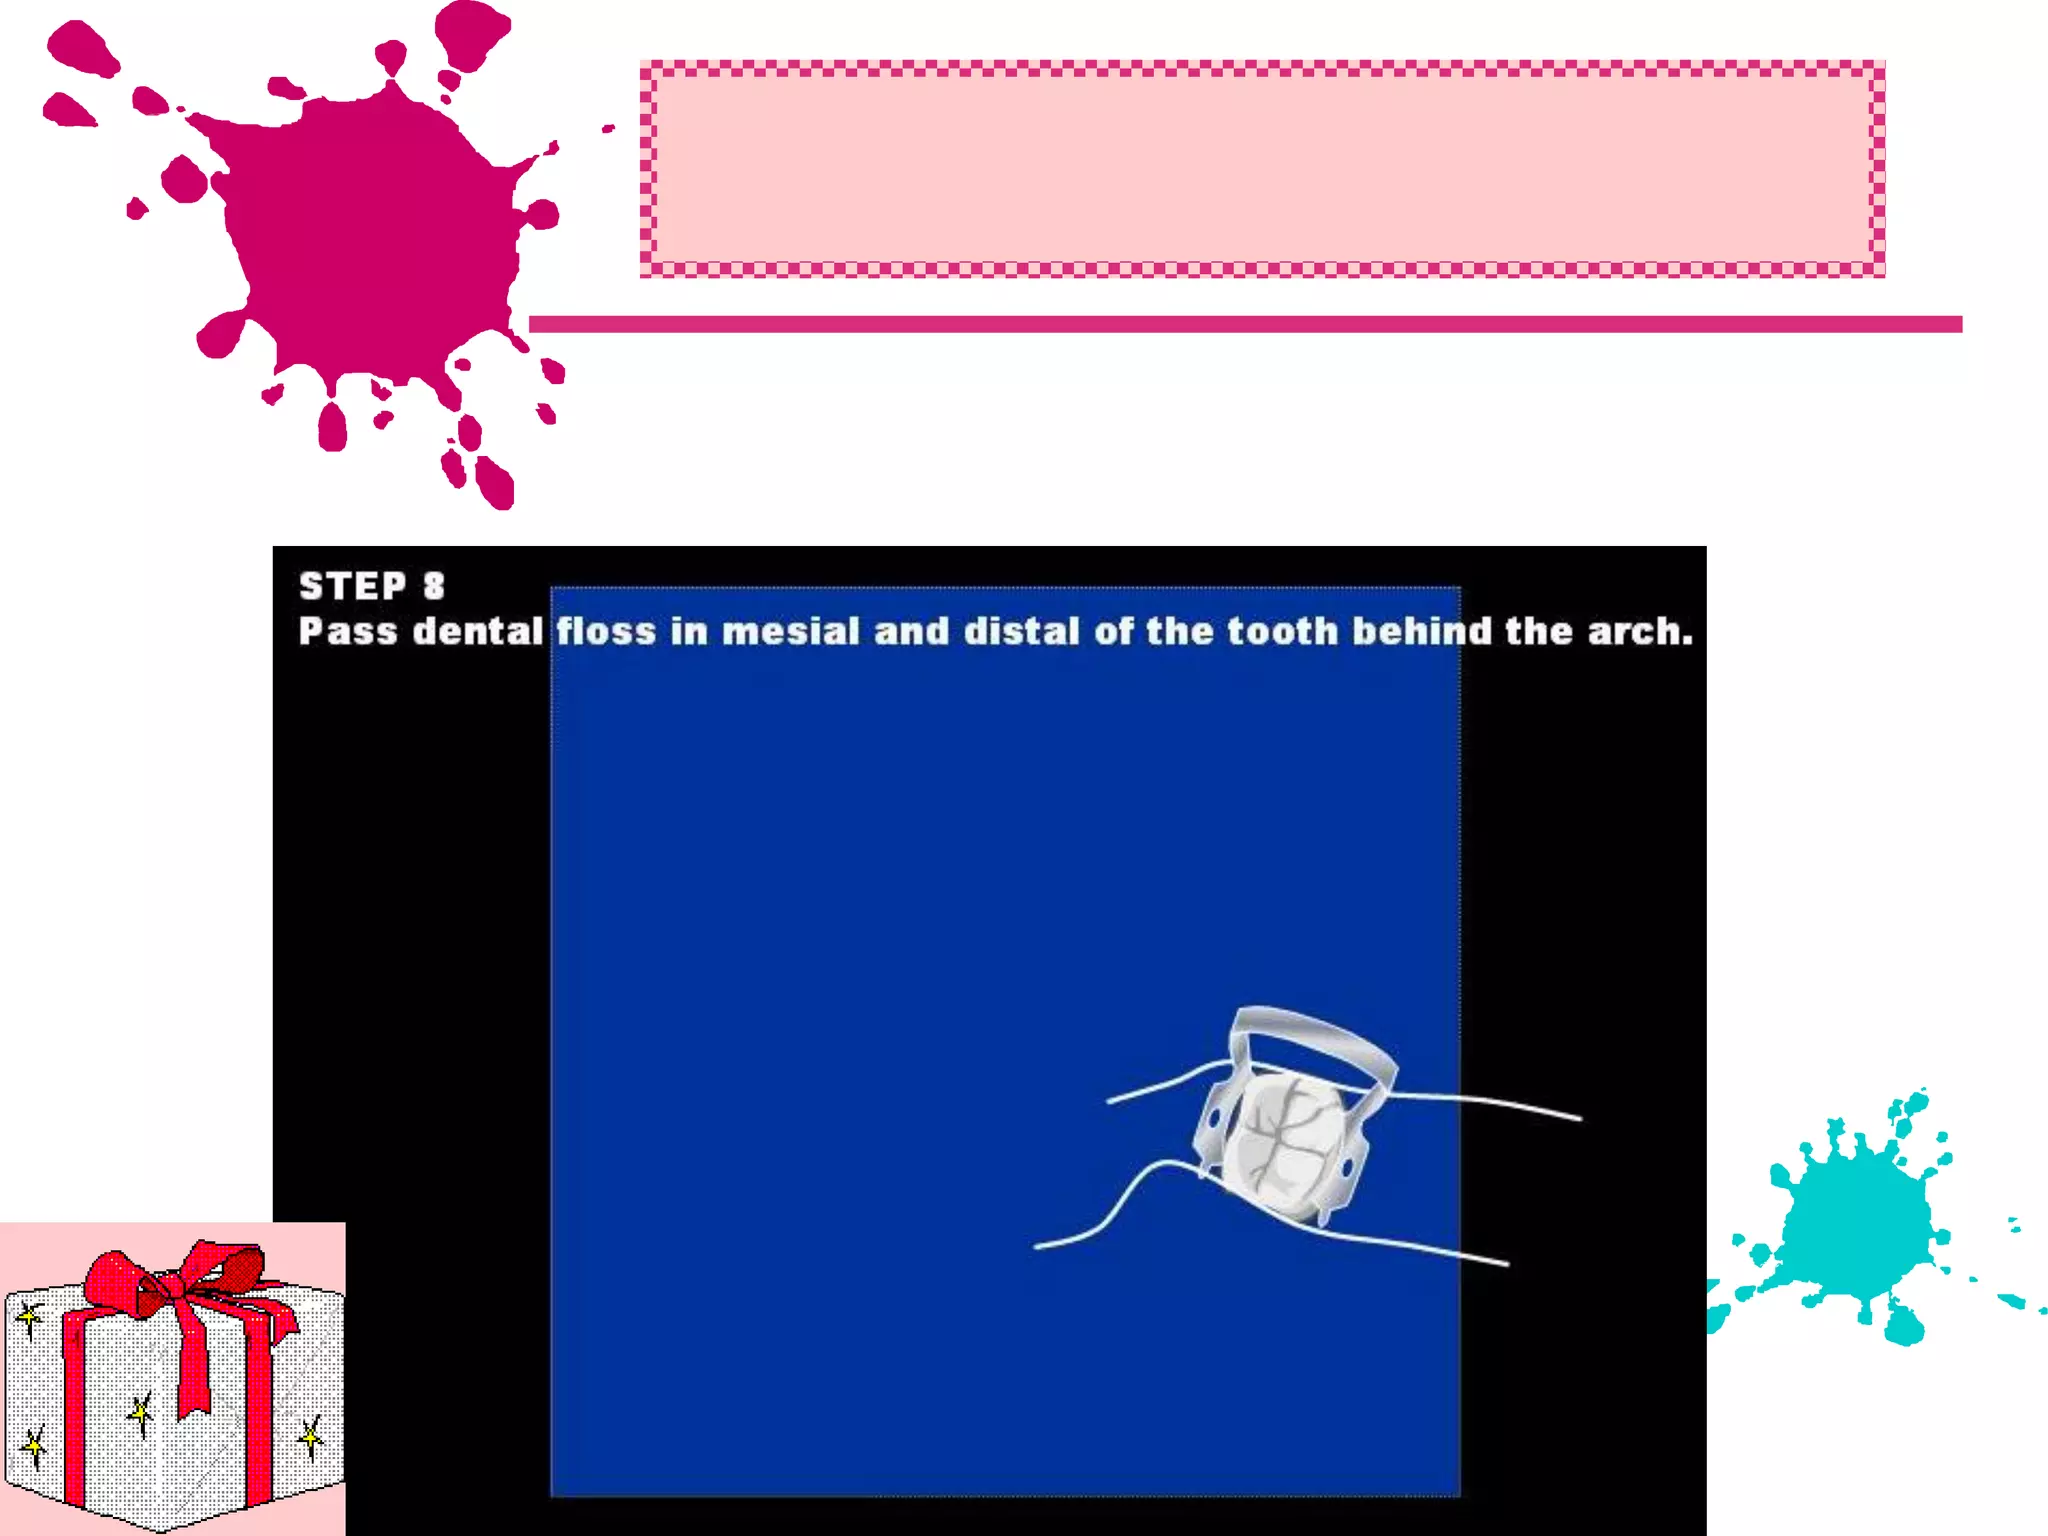

This document discusses the materials and components used for rubber dam isolation in dentistry. It describes the different types of rubber dam materials including color options and napkins to absorb moisture. It also outlines the tools needed such as punches to make holes, templates and stamps to guide hole placement, clamps to secure the dam, and other accessories like wedges and lubricant. Finally, it provides guidance on punching holes for different types of teeth and properly placing clamps in the rubber dam.